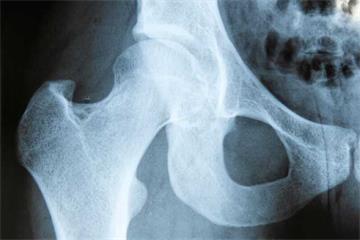

An initiative to give patients more tailored support before hip and knee surgery has won a national prize.